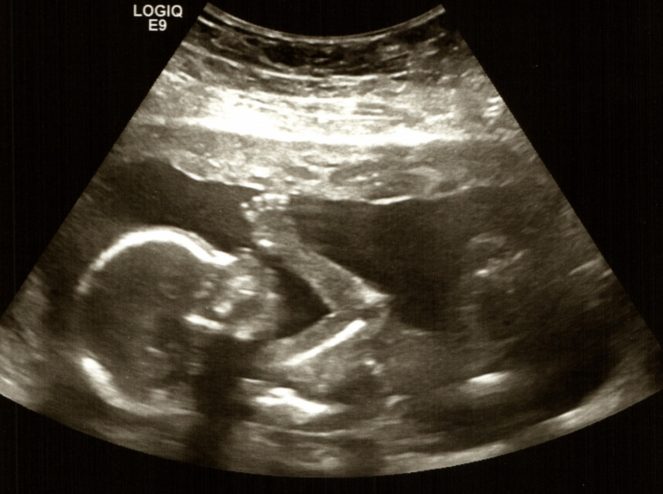

Count Down Until I Arrive